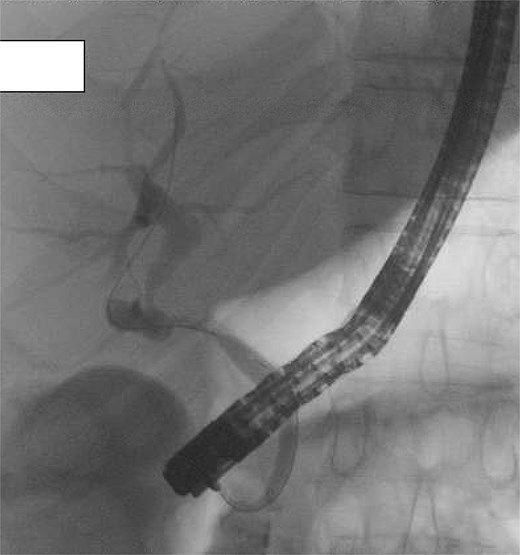

On post-operative day 5, the patient developed abdominal pain and CT cholangiogram suggested possible bile leak. Endoscopic retrograde cholangiopancreatography (ERCP) demonstrated the flow of contrast into an elongated infundibular-cystic duct channel with no obvious bile leak, filling defects or CBD stricturing (Fig. 3). A sphincterotomy was performed and a 7Fr pigtail stent placed. Symptoms worsened and repeat CT cholangiogram demonstrated large volume intra-abdominal free fluid. On return to theatre, a pinhole perforation in the gallbladder remnant was identified as the source of bile leak, necessitating hepaticojejunostomy. A re-look laparotomy was performed 2 days later, after output >1 L of frank bile in the drain, where a revision hepaticojejunostomy with more proximal duct excision was performed using the Hepp-Couinaud technique [5] to manage anastomotic breakdown (Fig. 2C). The patient recovered well and was discharged. They remained well at 1 month follow-up. Histopathology demonstrated cholecystitis and cholelithiasis with no evidence of malignancy.

Post-operative ERCP demonstrating no filling defects, large stones, or extrinsic compression. Contrast drains from the liver into common hepatic duct and then via an elongated infundibular–cystic duct channel to the duodenum, supporting the diagnosis of a cholecystohepatic duct.